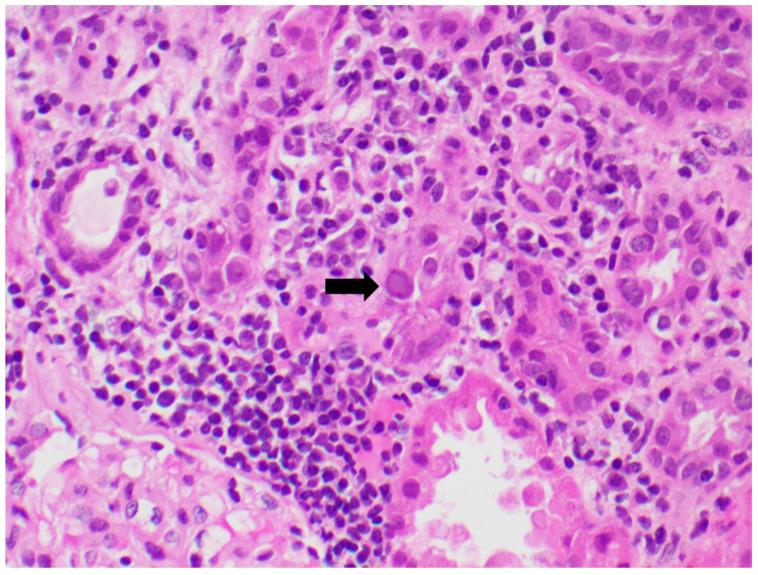

BK virus maintains a latent infection that is ubiquitous in humans. It has a propensity for reactivation in the setting of a dysfunctional cellular immune response and is frequently encountered in kidney transplant recipients. Screening for the virus has been effective in preventing progression to nephropathy and graft loss. However, it can be a diagnostic and therapeutic challenge. In this in-depth state-of-the-art review, we will discuss the history of the virus, virology, epidemiology, cellular response, pathogenesis, methods of screening and diagnosis, evidence-based treatment strategies, and upcoming therapeutics, along with the issue of re-transplantation in patients.

BK 病毒维持着一种潜伏感染,在人类中普遍存在。它在细胞免疫反应功能失调的情况下容易重新激活,在肾移植受者中经常被发现。对该病毒进行筛查可有效预防其发展为肾病和移植物丢失。然而,它可能是一个诊断和治疗方面的挑战。在本次深入的专题综述中,我们将讨论该病毒的历史、病毒学、流行病学、细胞反应、发病机制、筛查和诊断方法、循证治疗策略以及即将出现的治疗方法,同时还将讨论患者再次移植的问题。